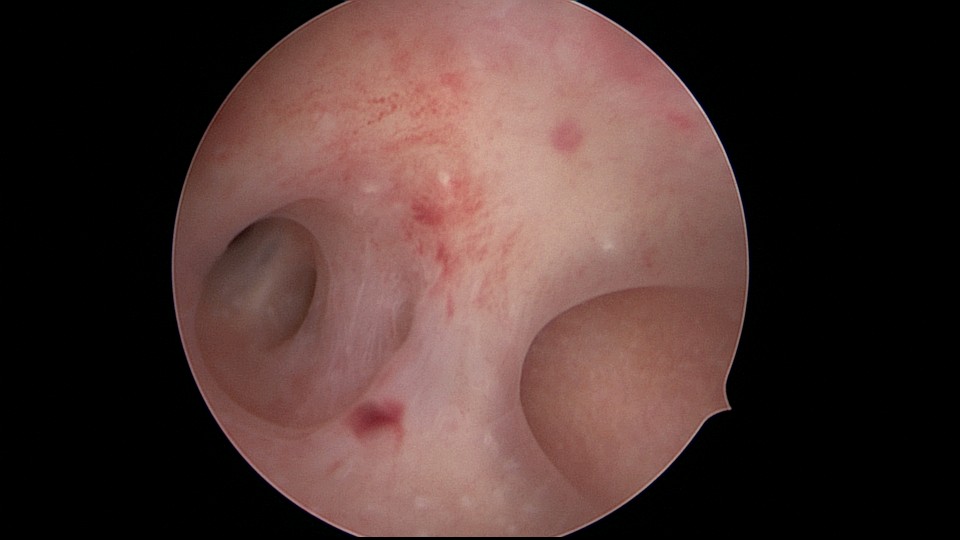

患者35岁,G5P0,继发不孕10年,10年前外院开腹宫外孕手术1次,试管失败1次。外院B超提示宫腔粘连,2021年4月在成都西囡妇科医院做宫腔镜检查,发现宫腔粘连。2021年11月到我院做宫腔镜分粘手术,术中见宫腔两侧及右侧宫角致密粘连,内膜片状充血,单极电切分粘,恢复宫腔形态,显露双侧输卵管开口。2021年12月宫腔镜二探取球囊,宫腔形态正常,双侧输卵管开口可见。分粘后再次试管成功,足月分娩。现40岁,G6P1。